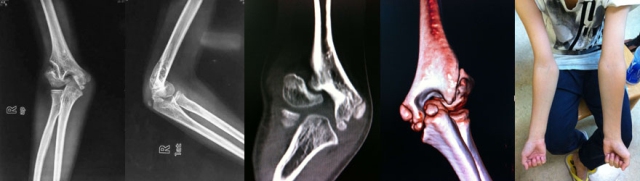

学生:12岁男孩,2岁时有外伤史,无原始片。因右肘外翻和提重物力量差就诊,体格检查右肘关节屈伸功能良好,没有神经受累症状。您的诊断?

老师:我考虑有两种可能,既往发生过肱骨外髁骨折或者肱骨远端全骨骺分离。两者的一个重要区别点就是是否存在外翻不稳定。如有明显的外翻不稳定,则多数情况下应该是陈旧外髁骨折。如果只有外观外翻而没有外翻不稳定,则有可能是很小时候发生的肱骨远端全骺分离长期塑形的结果,也有不愈合的可能,但后者可能性很小,陈旧外髁骨折的可能性大。

老师:手术目的包括“促进不愈合处愈合+肘外翻畸形矫正”,我会做骨折处的原位加压融合+低位肱骨髁上截骨。一个很重要的原则就是不要做切开复位,不要为了试图做切开复位而过度显露剥离不愈合处,否则可能会严重影响骨块的血运,因为肱骨外髁骨块血供主要来自于后方。